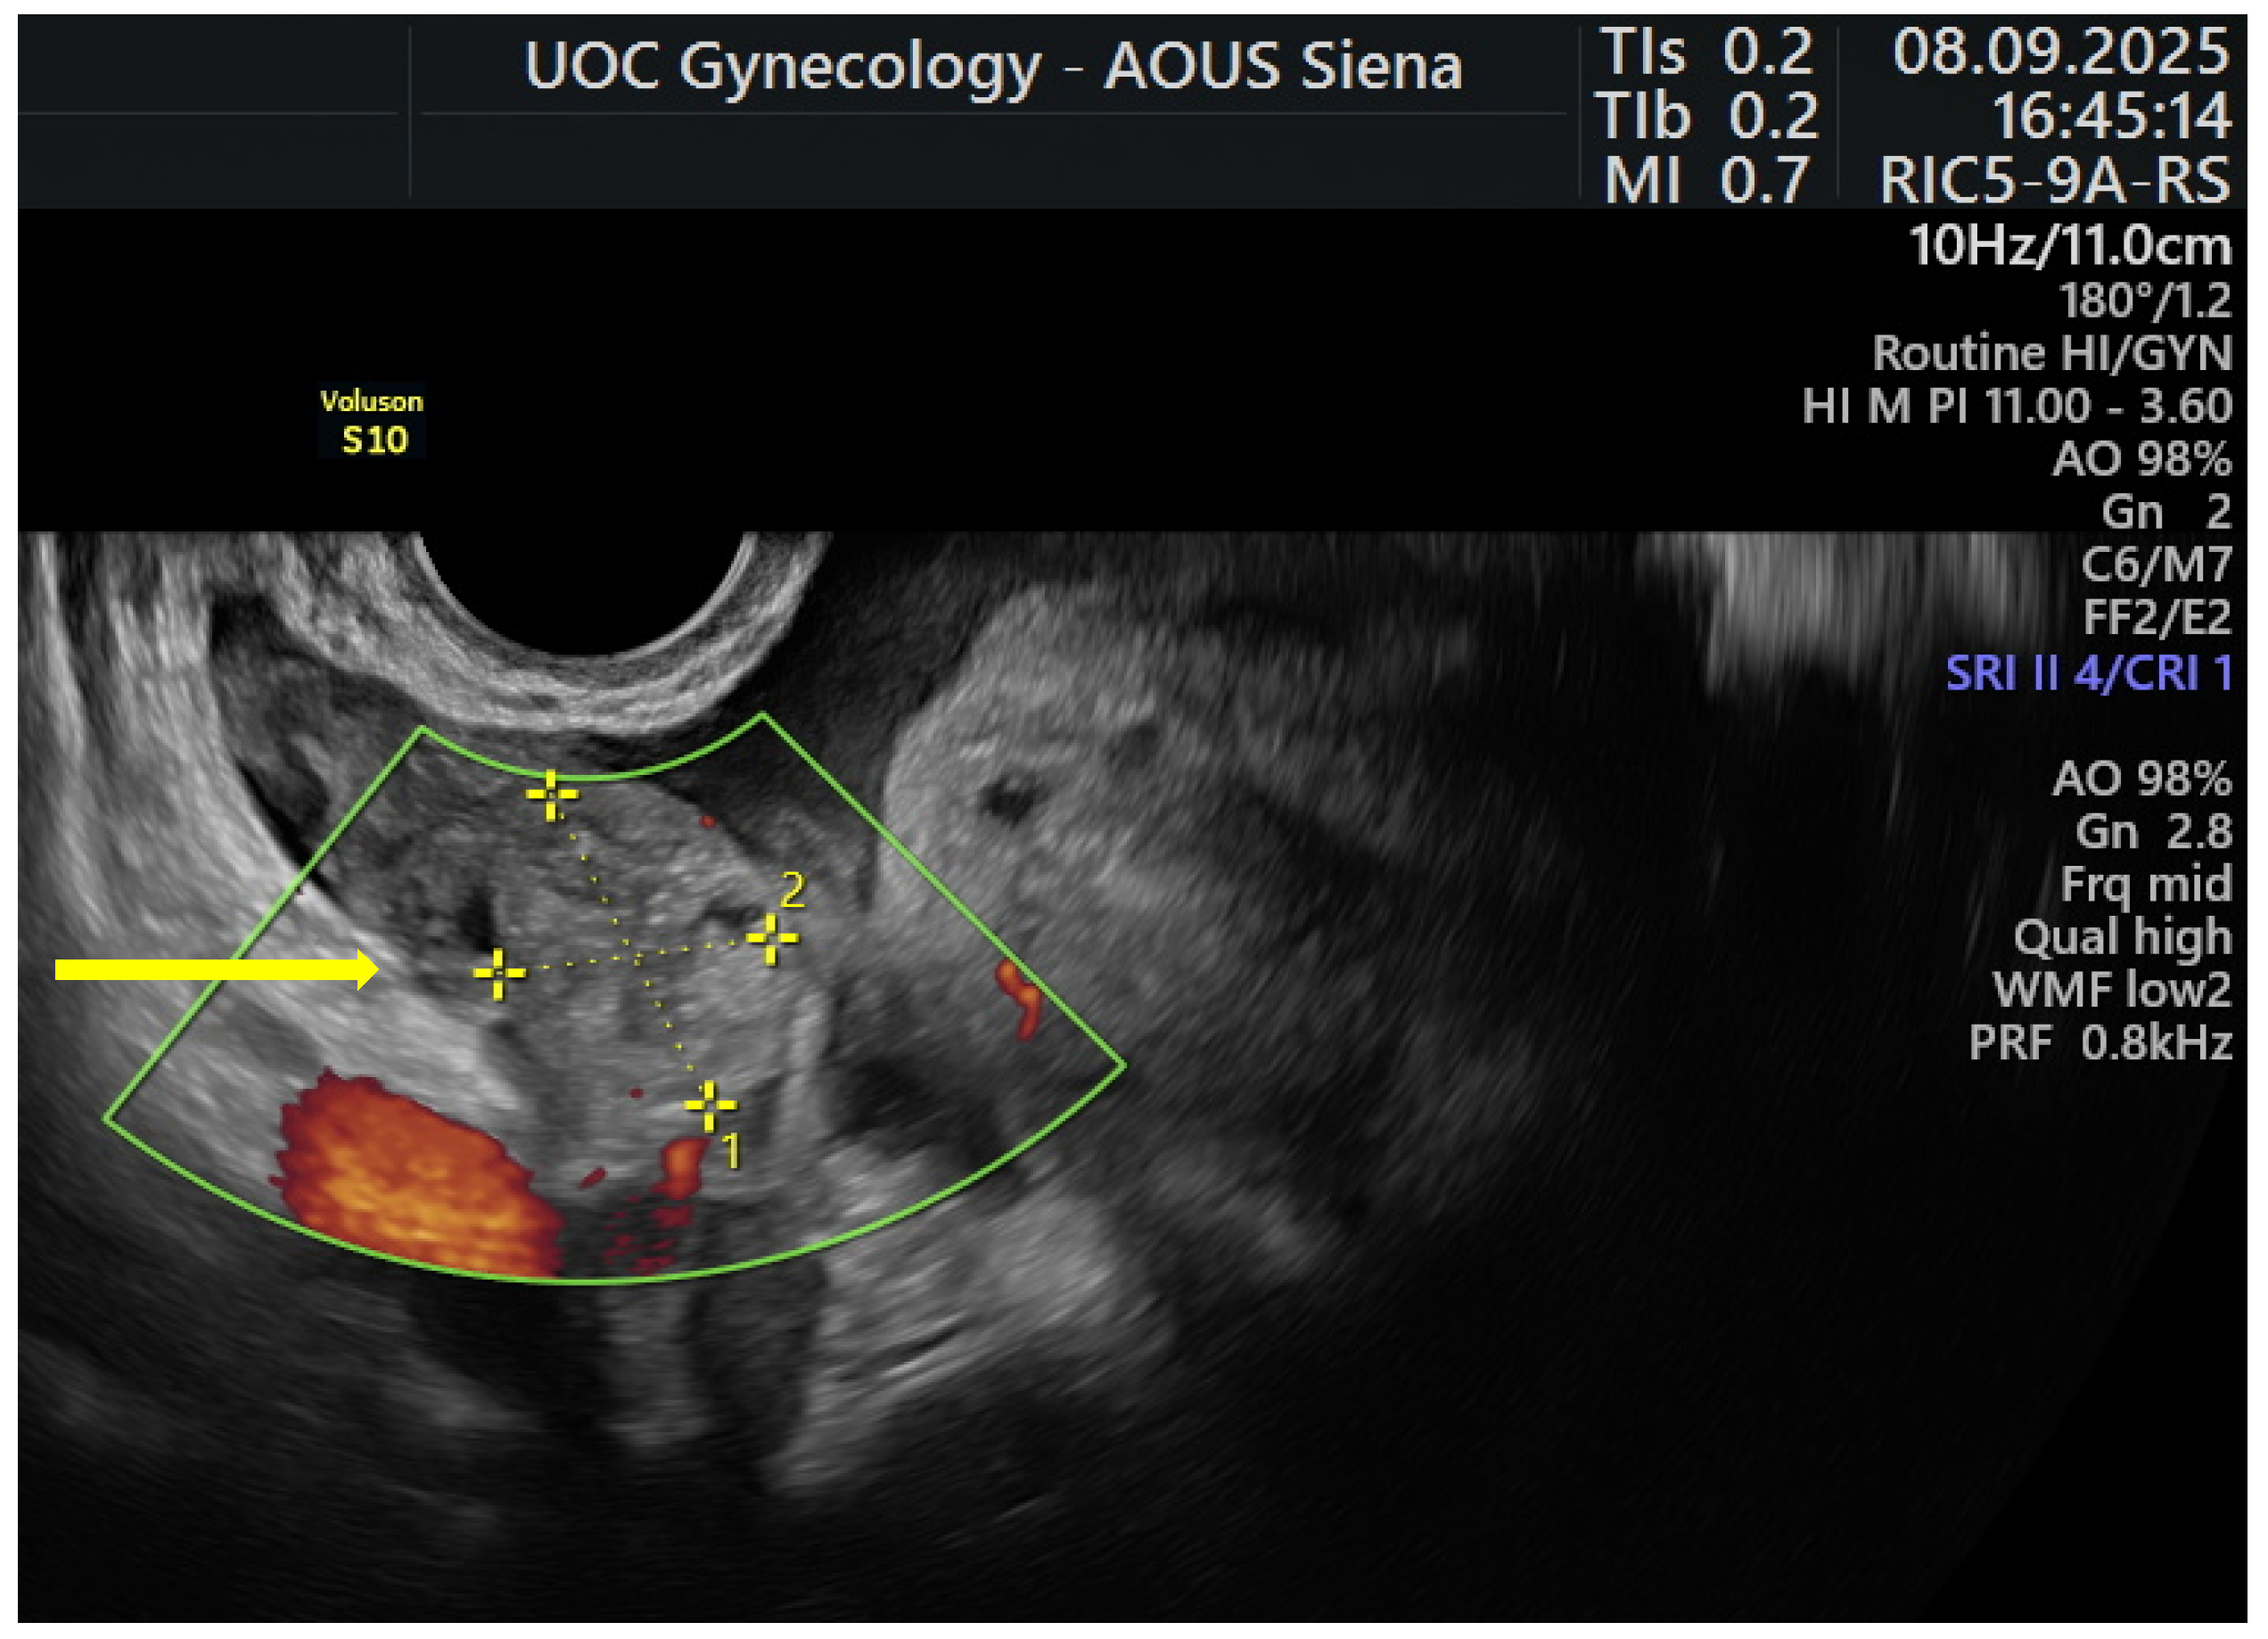

2. Case Presentation

| Present case | 39 | Multiparous | Adenomyosis | 19.5 mg | In situ | Right tubal | 18 months |